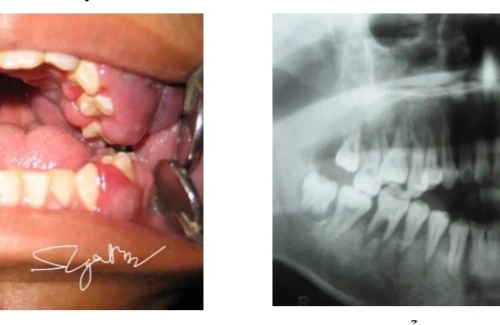

Đi khám viêm lợi, nam sinh 16 tuổi được phát hiện ung thư máu